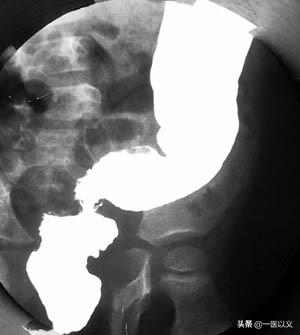

一方、バリウム注腸は中等度から進行性の潰瘍性大腸炎患者の診断に重要な役割を果たしている。腸粘膜の浮腫や潰瘍が認められる。

潰瘍性大腸炎の診断基準:①桿菌性赤痢、アメーバ性大腸炎、住血吸虫症、腸結核、クローン病、放射線性腸炎およびその他の大腸の炎症の原因を除外する、②典型的な臨床像があり、少なくとも内視鏡検査またはX線検査で1の特徴的な変化が認められる、③臨床症状は典型的ではないが、典型的な大腸内視鏡検査またはX線検査、あるいは生検による病理学的検査が行われ、潰瘍性大腸炎であることを確認できる